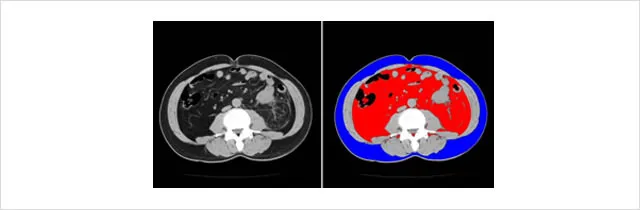

お臍の部位での内臓脂肪量をCTで測ります。これが100cm2を超えると、高血圧、脂質異常、高血糖といった動脈硬化の危険因子を持つことが多くなります。特定健診の男性85cm以上、女性90cm以上の腹囲の基は、100cm2に相当する腹囲を男女別に調べて決められました。

※赤部が内臓脂肪、青部が皮下脂肪(下記写真)